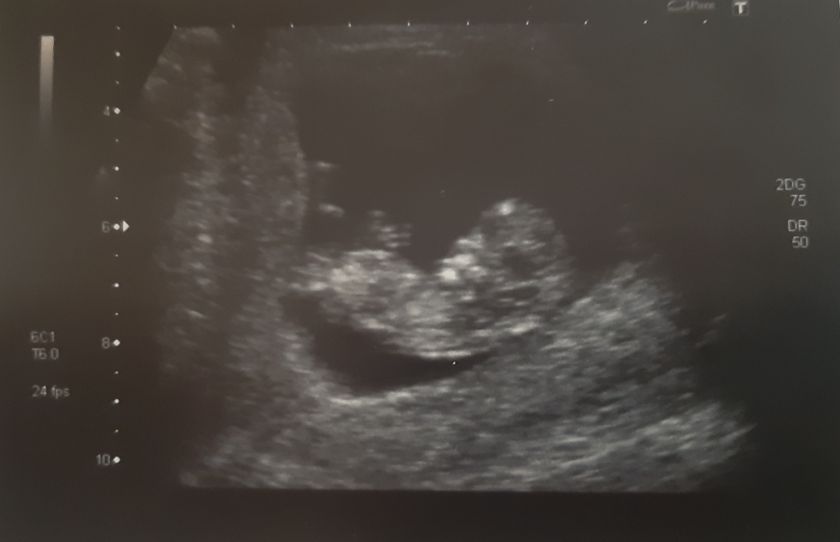

Сходили мы с мужем… увидели наконец наше чудо ?

КТР 46 мм

Бипариентальный размер 17 мм

Окружность головы 66 мм

Окружность живота 53 мм

Бедро 5 мм

ТВП 1,4 мм

Носовая кость визуализируется

ЧСС 165 уд/мин

Хорион по передней стенке

Ручками-ножками нам махали, сердечко послушать и посмотреть дали.

По месячным срок 11 недель 5 дней (ПДР 10.06.20), по УЗИ срок 11 недель 2 дня (ПДР 13.06.20). В ЖК ставят ПДР 11.06.20.